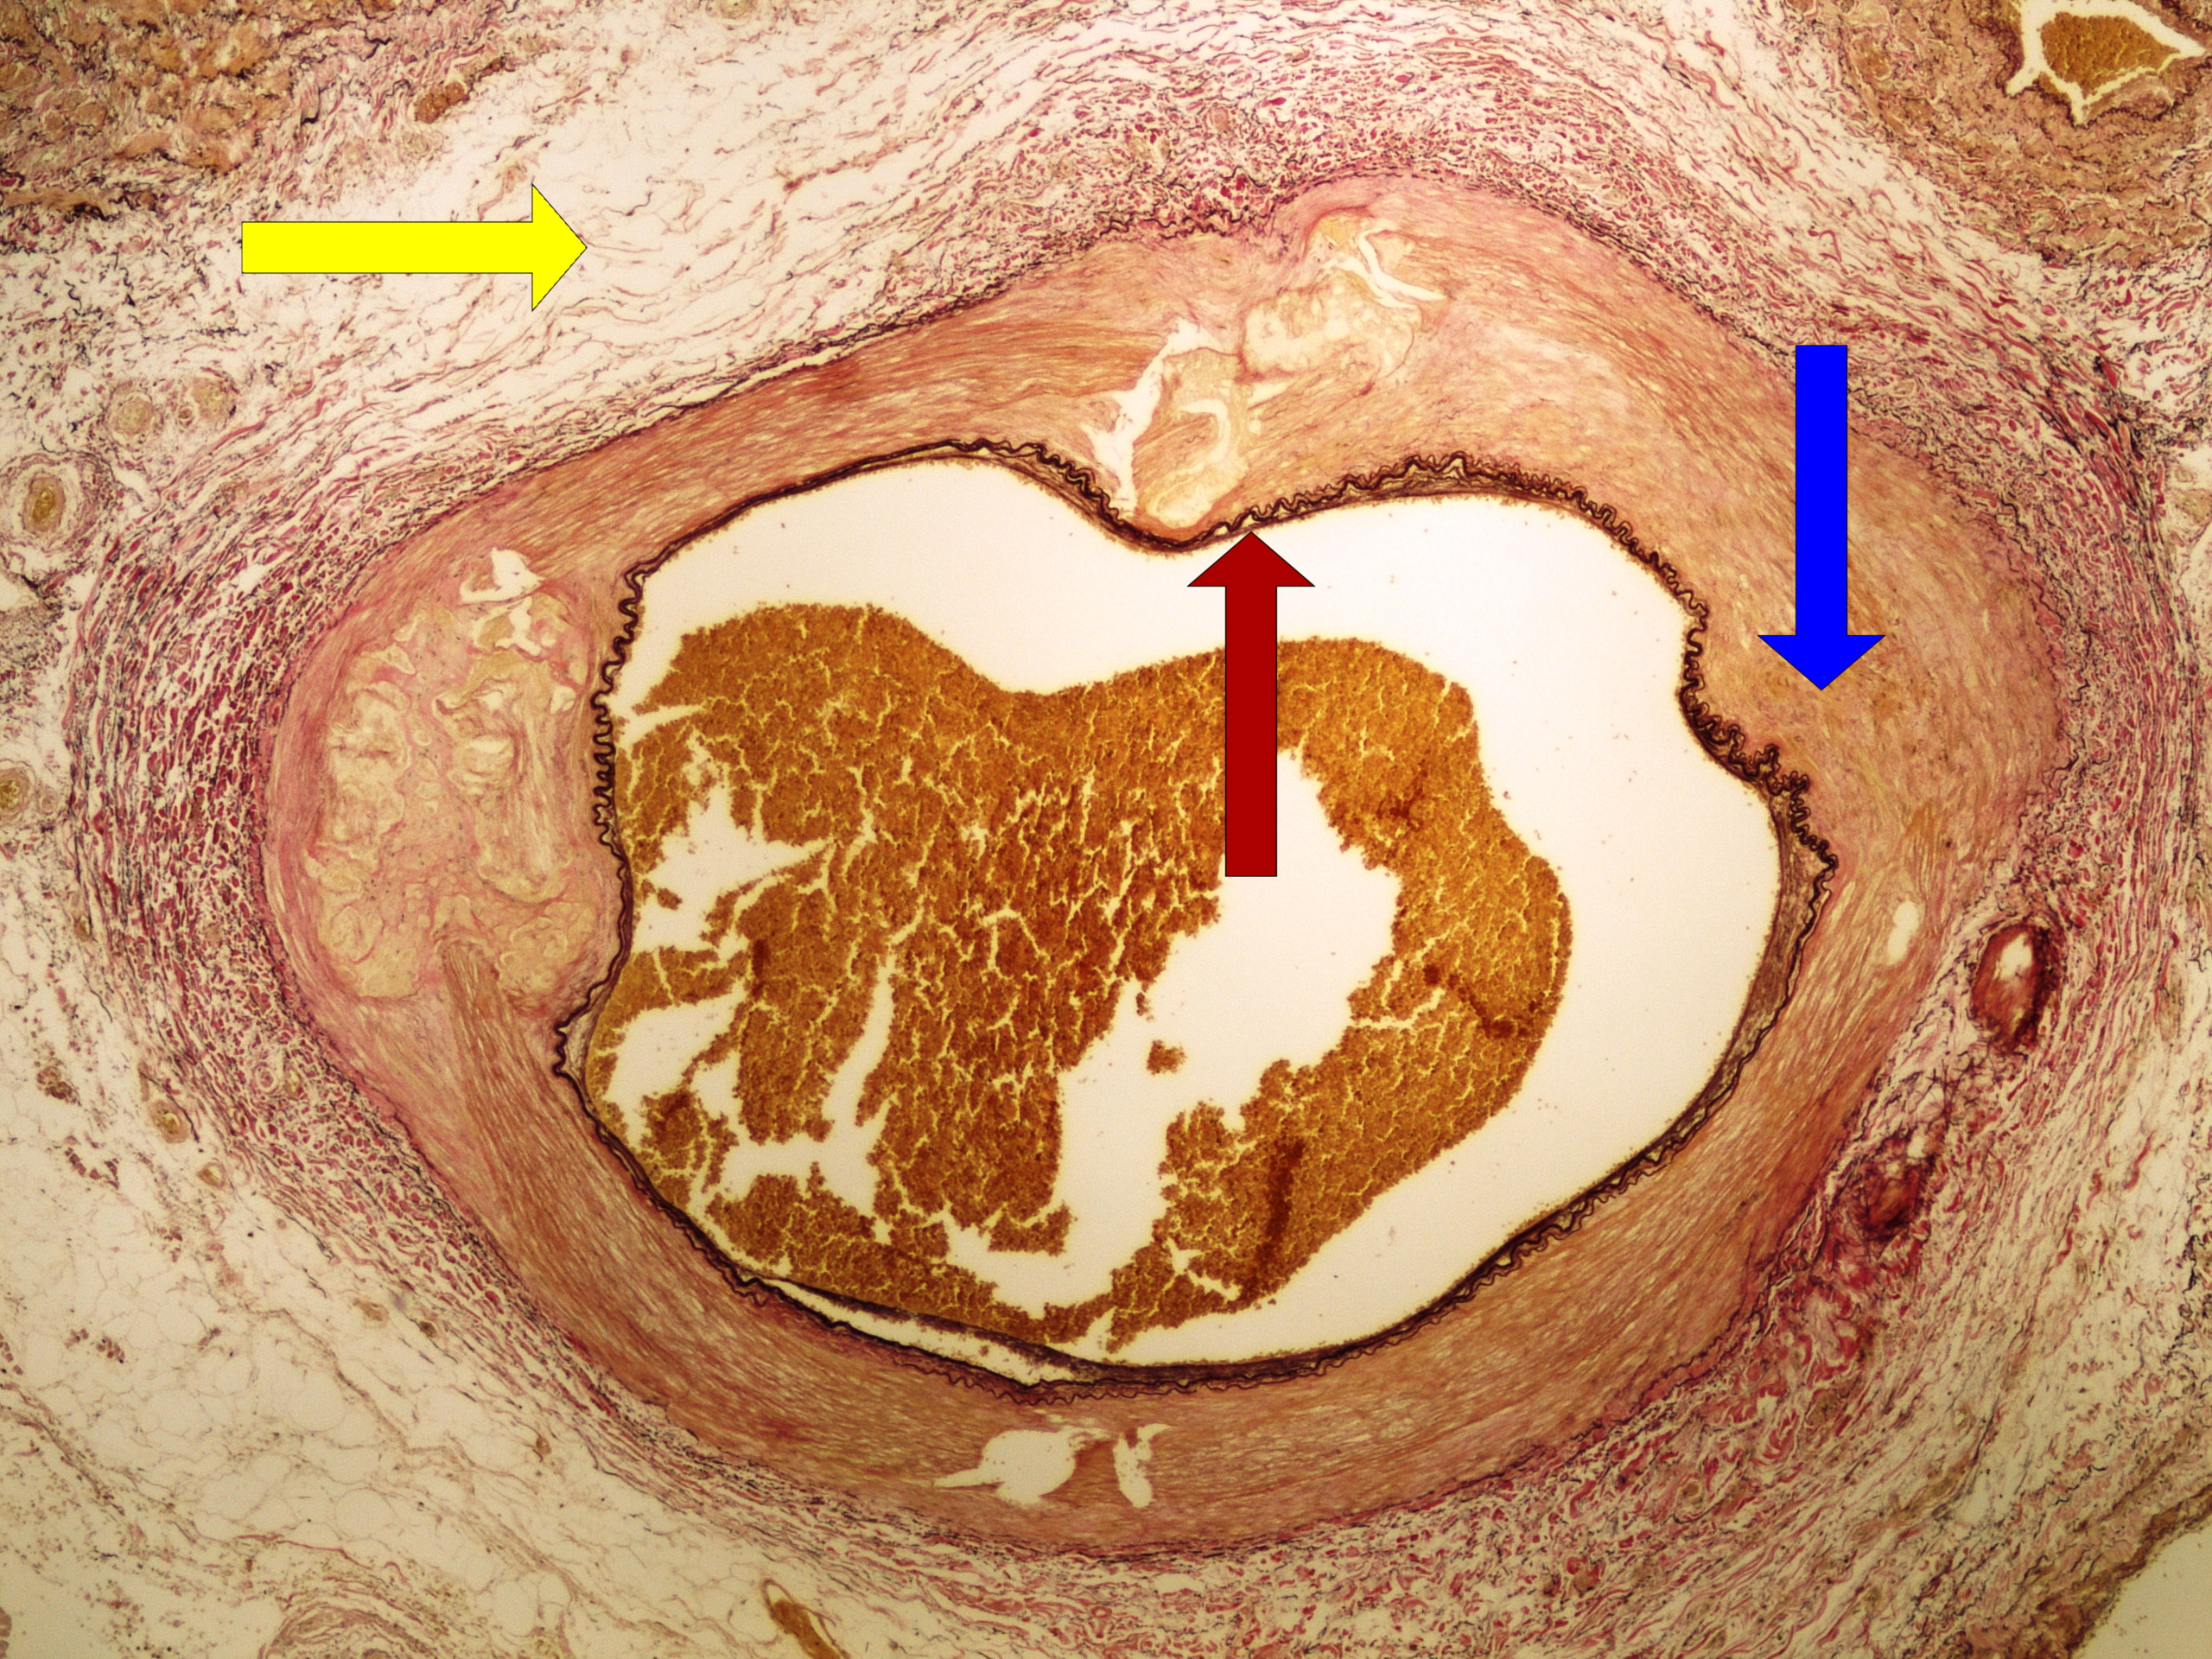

Preparát č.1 a č.2 - barvení van Gieson (elastická vlákna)

Struktury

- tunica intima

- tunica media

- tunica adventitia